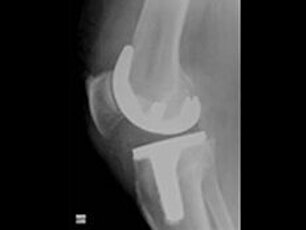

Kniegelenksprothetik

Als Kniegelenksarthrose (Gonarthrose) wird der Verschleiß des Knorpelüberzugs im Kniegelenk mit seinen Knorpelflächen der Oberschenkelrolle und des Schienbeinkopfes bezeichnet.

Dies führt zunehmend zu Schmerzen im Knie und schließlich auch zu einer Bewegungseinschränkung. Ursachen können eine unkorrekte Beinachse, eine alte Knieverletzung, Übergewicht oder anderweitig übermäßiger Verschleiß des Knies sein.

Ist nur die innere Gelenkfläche betroffen, kann man eine sogenannte Schlittenprothese als Knorpelersatz einbauen. Ist das gesamte Kniegelenk betroffen, wird eine Knie-Total-Endoprothese implantiert (Knie-TEP). Die Operation und erste Nachbehandlung erfolgt unter Einlage eines Schmerzkatheters. Die Vollbelastung des operierten Beines wird so früh wie möglich angestrebt. Die Ärzte implantieren jährlich etwa 400 Knieprothesen; sie verfügen damit über sehr viel Erfahrung und Routine bei dieser OP.